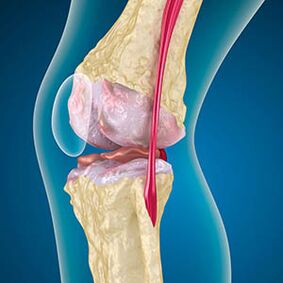

With arthrosis, the cartilage lining the edges of the bones is abrasion or completely absent.Damaged tissue is not a source of pain, because it does not have receptors.Inflammation in nearby structures causes characteristic symptoms.

The body continues the regeneration of damaged tissues, but the cartilage grows unevenly.As a result, irregularities are formed that injure other elements of the joint.The nature of osteophytes is explained by compensation for smooth joint cartilage.Another version indicate that the growth of "spurs"It is associated with an attempt to stabilize the joint medially or lateral due to muscle weakening.

Swelling is caused by injury to soft tissues, inflammation of the tendons and joint bag.The appearance of heat in the knee, swelling indicates the accumulation of inflammatory exudate -Arthrosis is often accompanied by bursitis, synovites, tendinitis.

With low effectiveness of drugs, patients are offered arthroscopy- a minimally invasive procedure for the removal of bone growths, audit of the joint.If necessary, surgeons carry out ligaments and cartilage plastic, remove the foci of worn -out fabric.